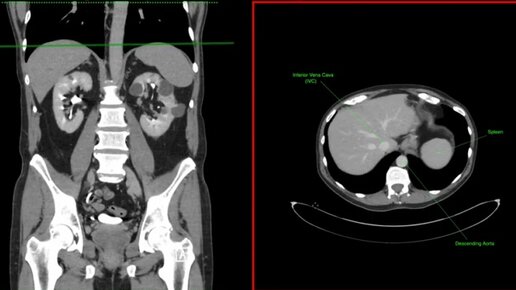

Что видно на КТ брюшной полости и малого таза